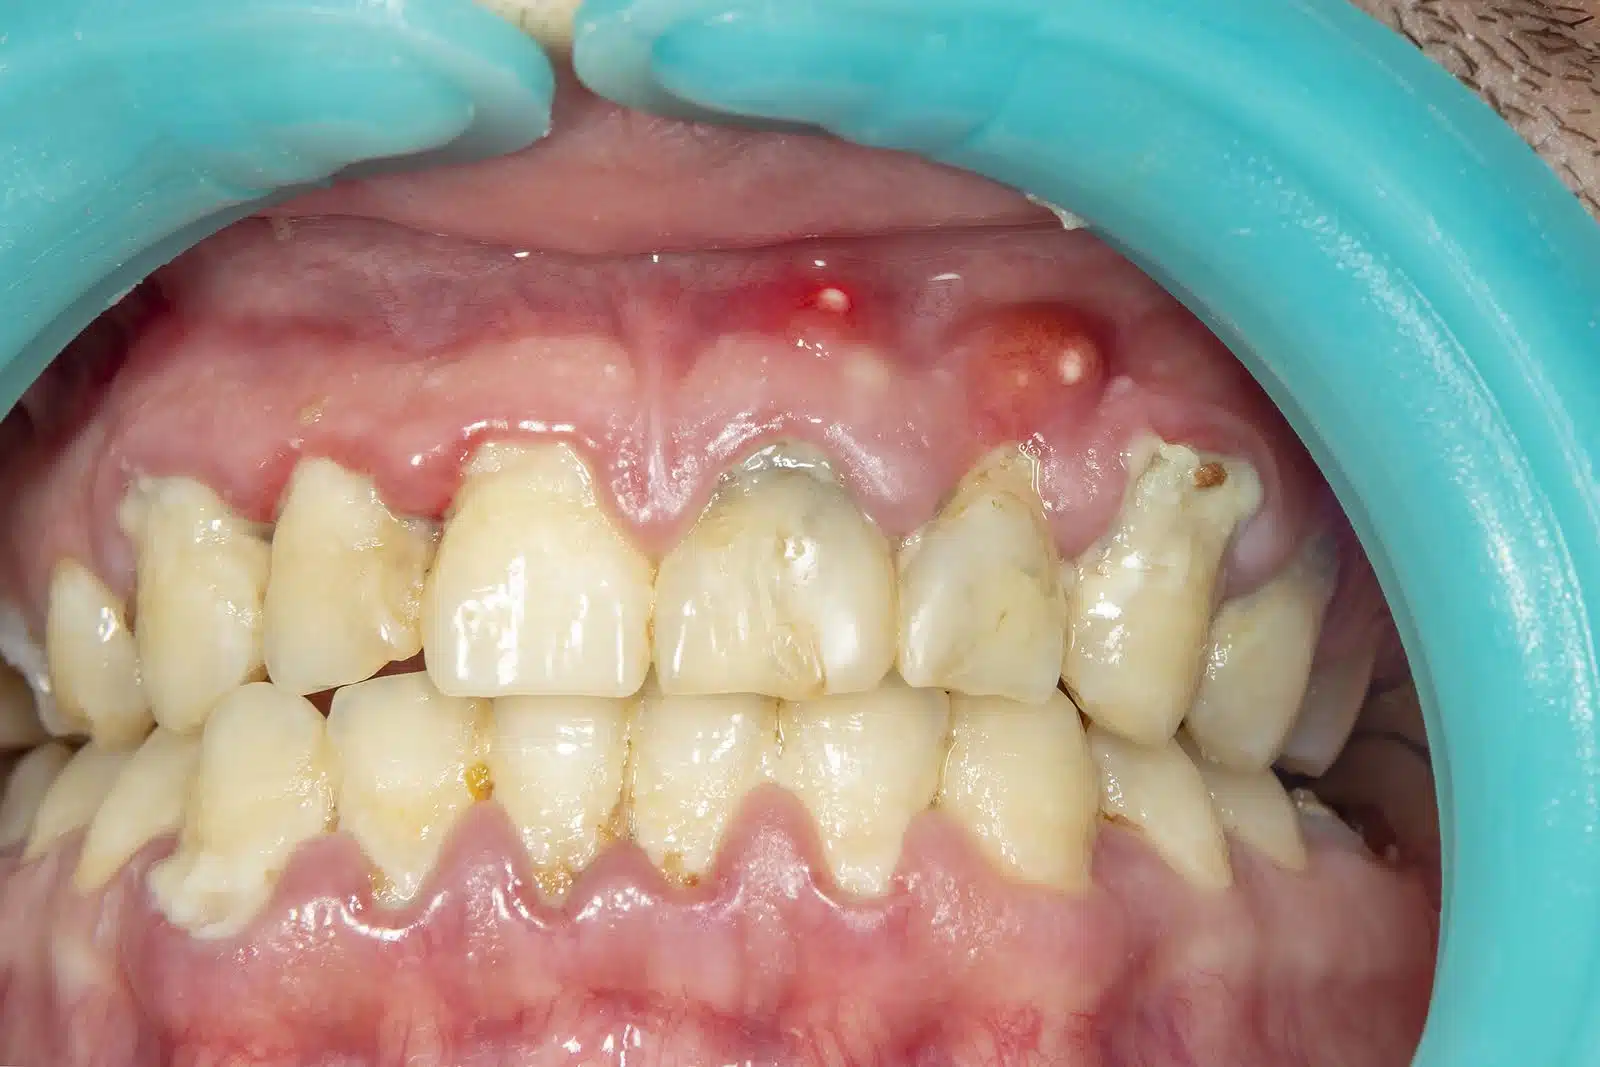

Swollen Gums With Orthodontic Treatment — When to Call a Professional

Swollen gums with orthodontic treatment should be checked if they remain tender, bleed often, or appear shiny and enlarged. Pain, persistent redness, or gums growing over brackets are also warning signs. Early care can prevent infection, protect the gums, and keep treatment moving forward without added setbacks.